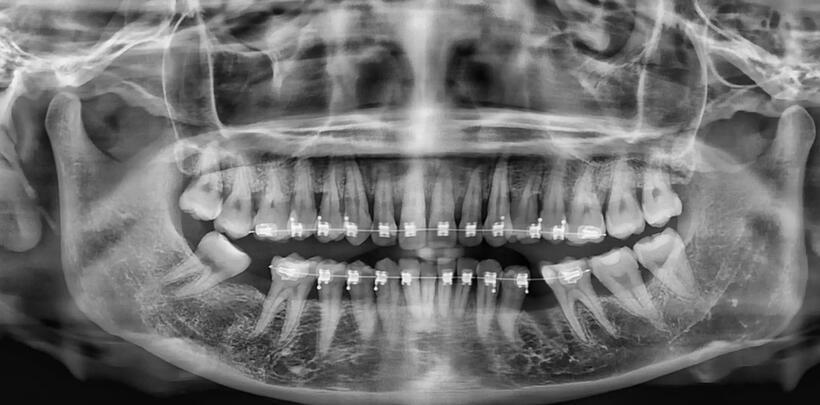

Hình ảnh X Quang thể hiện D bị mất 2 răng khi đi chỉnh nha. Ảnh: BSCC

Hình ảnh chụp phim thể hiện, D mất 2 răng hàm dưới , viêm nha chu dẫn đến tiêu xương ổ răng theo chiều ngang nhiều răng